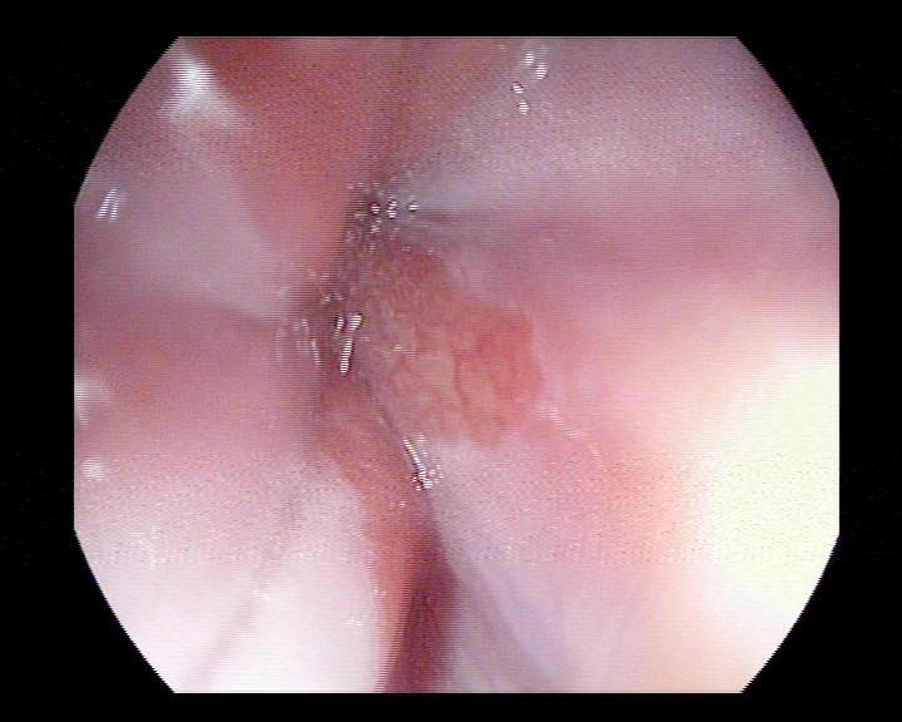

Nội soi đường tiêu hóa trên và làm sinh thiết tế bào giúp các Bác sĩ xác định được người bệnh có mắc Barrett thực quản hay không và mức độ tiến triển của bệnh thế nào để có những phương pháp điều trị hợp lý và chính xác. Phần lớn barret thực quản không có loạn sản, người bệnh nên nội soi định kì 6 – 12 tháng để theo dõi sự tiến triển của các tế bào trong thực quản.